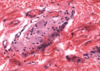

Kupffer cells - system of macrophages, known as Kupffer cells (KC), are found interspersed among the endothelial lining cells of Liver sinusoids (Si). these macrophages are larger than the epithelial cells and may be recognized by the presence of phagocytosed material within them. Kupffer cells may be demonstrated by injecting an animal intravenously with indian ink, as in this specimen. Some cells appear as large black smudges because they are filled with phagocytosed ink (arrows), whereas other cells possess only small quantities of the phagocytosed material (arrow heads). Note that much of the sinusoidal lining devoid of ink, indicating that the endothelial cells are probably not phagocytic.